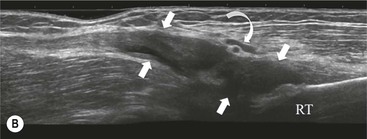

The distal biceps tendon inserts on the tuberosity of the proximal radius. It does not have a tendon sheath, but surrounding connective tissue is known as a paratenon. It is surrounded near the insertion by the bicipitoradial bursa. Distal biceps tears are often clinically unrecognised, but may be amenable to surgery if diagnosed early. In the early stages the tendon is thickened and there may be an effusion in the bicipitoradial bursa (Fig. 46-18). In complete rupture the tendon retracts proximally. MRI and US may be used to confirm the diagnosis and locate the tendon end (Figs. 46-19 and 46-20).